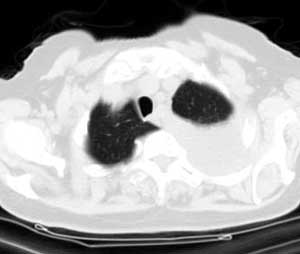

标题: CT0563:病历讨论,胸膜间皮瘤?

测ct值3-6hu,

既然ct值是3-6hu,还不如考虑包裹性积液。

请上传纵隔窗。目前还是支技包裹性积液(明显梭形),即使是间皮瘤并积液也少梭形的。

从图片看,包裹性积液好象更合理,梭形,ct值3-5hu(在哪看到的?);胸膜间皮瘤如此规则,不多见。

左侧背部胸膜肥厚,伴包裹性积液,不考虑间皮瘤.

同意以上各位的高见,首先考虑包裹性积液,1.胸膜间皮瘤积液量一般较大,以游离性积液更为常见,2.可以看到增厚的胸膜结节